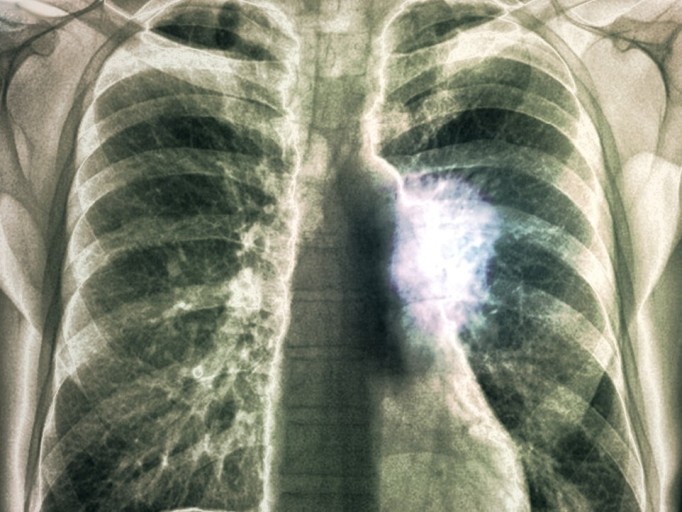

폐렴 증상 폐렴은 폐의 세균, 바이러스, 곰팡이 등 감염으로 인해

폐포(폐 속의 공기 주머니)에 염증이 생기고, 고름이나 액체가 차는 질환입니다.